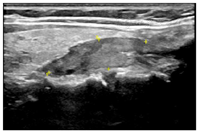

入院后行甲状腺超声示甲状腺左叶上、下极深方甲状旁腺区见2个囊实性结节,大小分别为2.9cm×1.4cm×1.1cm、2.3cm×1.4cm×1.2cm,均形态规则,边界清晰,CDFI:内见较丰富血流信号(图1,图2,图3,图4)。行甲状旁腺融合显像(显像剂:99Tcm-MIBI)示甲状腺左叶上极后上方见结节样显像剂浓聚灶,相应CT层面示椭圆形软组织密度影,边界清,大小约27.6mm×18.2mm×16.0mm。CT另见甲状腺左叶下极后下方一椭圆形软组织密度影,边界较清,大小约25mm×13.7mm×12.5mm,相应ECT层面未见显像剂摄取(图5,图6)。行嗜铬细胞瘤融合成像(显像剂:131I-MIBG)示颈部及腹部可见显像剂摄取病灶(图7,图8)。

超声图像中左侧甲状旁腺区2枚囊实性结节形态、回声、位置及血流均相似,结合实验室检查及临床病史,均提示为甲状旁腺腺瘤,但甲状旁腺融合成像仅支持甲状腺左叶上极后方结节为甲状旁腺腺瘤。甲状腺左叶下极后方结节无99Tcm-MIBI显像剂摄取,但有131I-MIBG高摄取,故综合以上考虑甲状腺左叶上极后方结节为甲状旁腺腺瘤,左叶下极后方结节为副神经节瘤。